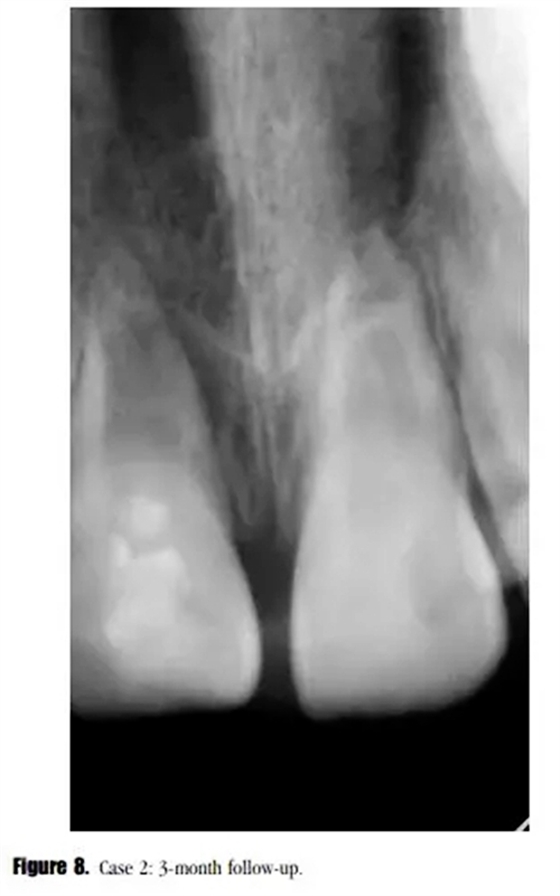

盡管在3個月的隨訪中,瘺管沒有消失,但是牙齒的癥狀已經(jīng)消失了。X線顯示根尖區(qū)的進一步發(fā)育,牙根近中方向有透射性影響。與患者家長溝通后,1個月后實行常規(guī)根管治療。根尖區(qū)放置5mm后的MTA栓,復(fù)合樹脂以及纖維加強樁修復(fù)。少量的MTA從根尖近中方向被壓出。此外,根管系統(tǒng)以及繼發(fā)生成的根尖組織之間可見一明顯的透射影像。(圖8)

在3個月的隨訪中,患者癥狀消失,X線顯示透射區(qū)愈合(圖9)